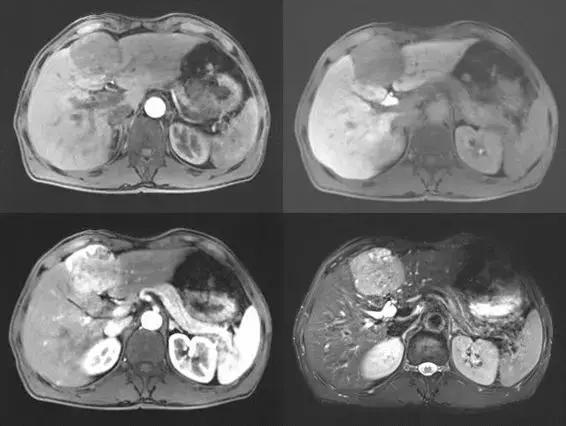

术前影像学检查(2018.8.25)

*肿块约为58mm*50mm*50mm。

术后2+月影像学检查(2018.11.6)

*肿块缩小至35mm*31mm*29mm大小。

术后2+月影像学复查,病灶明显缩小,并证实原先大的单发病灶实际是由2个病灶融合而成,肝右叶未见碘油沉积,证明肝右叶无肿瘤发生,因AFP存在高值,考虑与原发灶相关,经讨论及为验证载药微球的栓塞效果,说服患者接受外科彻底完整切除。